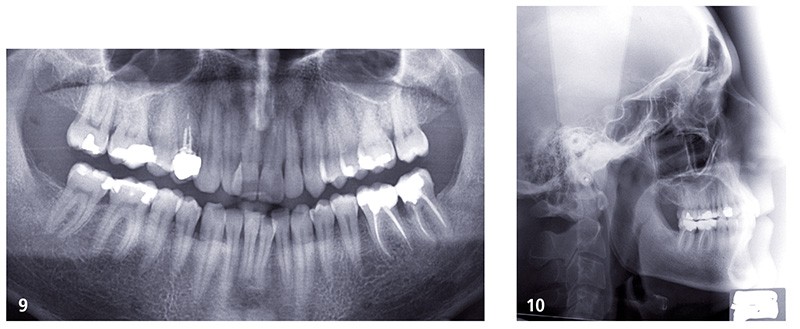

Le patient a choisi d’être appareillé en technique linguale Incognito©. L’appareillage a été posé avant l’extraction de 24 (fig. 11 et 12) et un cache fabriqué pour masquer le site d’extraction (fig. 13 et 14). Ce cache est ensuite régulièrement meulé au fur et à mesure du recul de 23 (fig. 15 et 16).